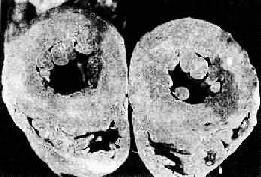

图8-13 高血压病之脑出血

大脑左侧内囊出血并破入侧脑室